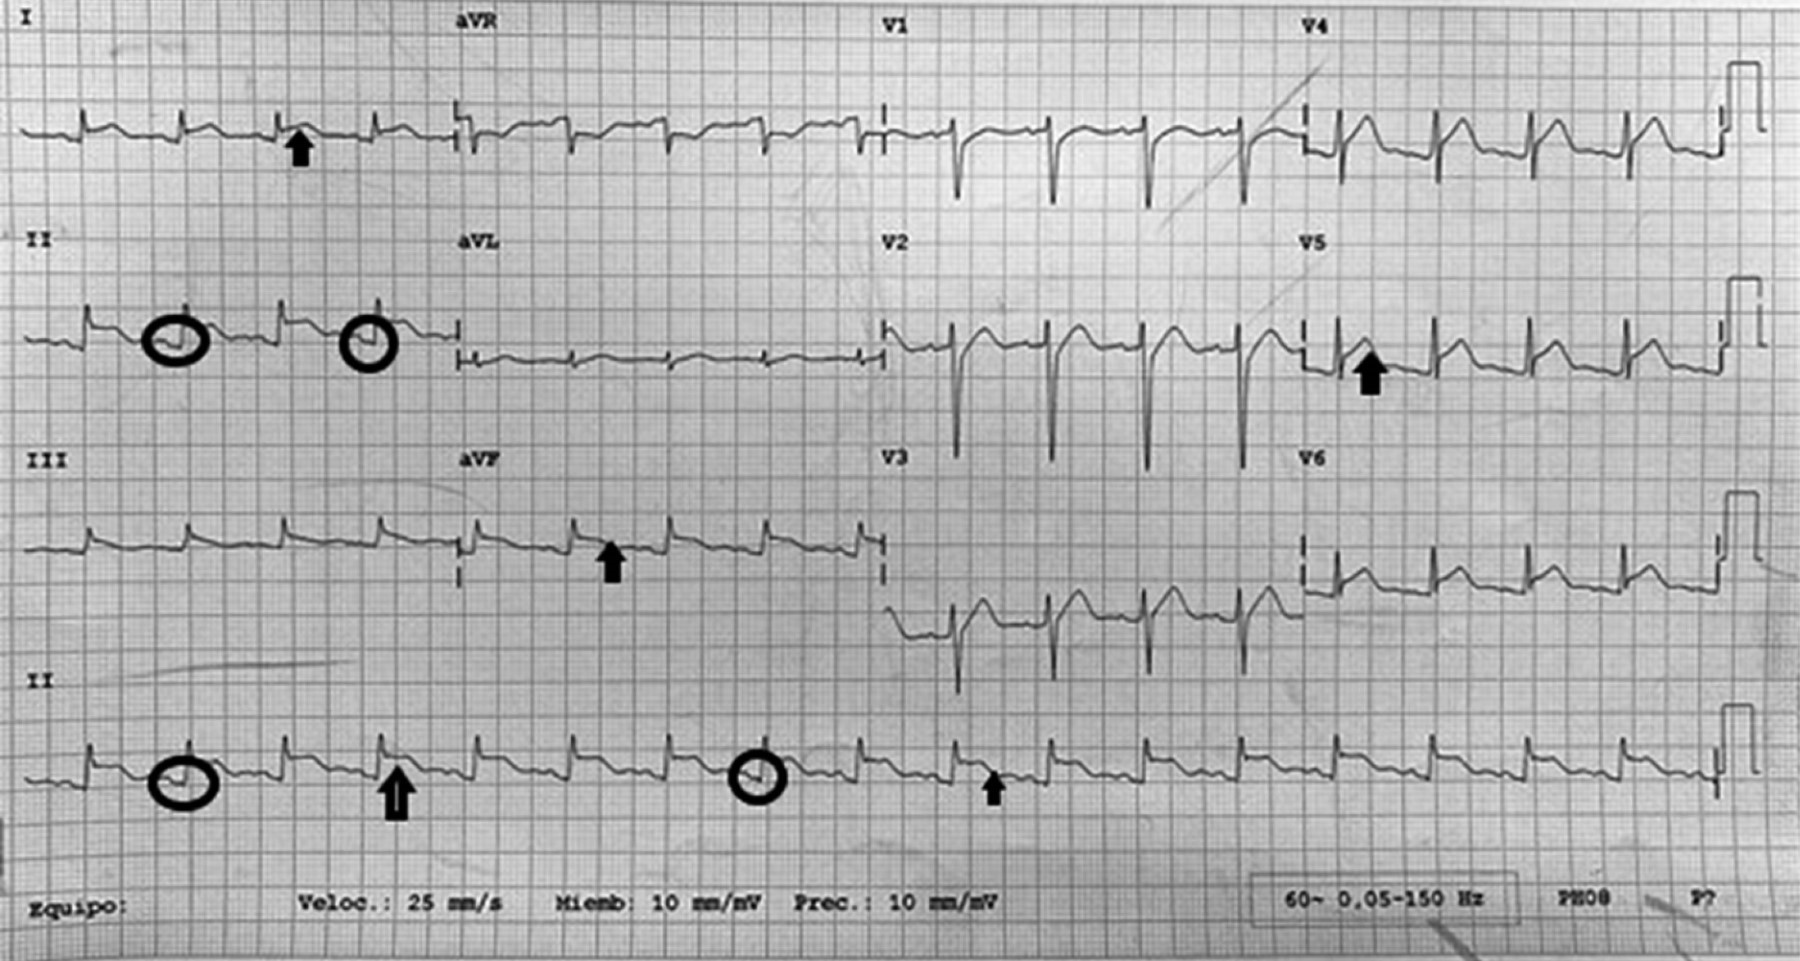

Diabetic ketoacidosis, hypokalemia and supra ST-segment elevation

Introduction: ST-segment electrocardiographic changes in patients with diabetic ketoacidosis (DKA) have, to date, only been described in the adult population. Case presentation: a 13-year-old female patient with obesity experienced her first episode of DKA, classified as severe (pH 6.89, HCO3 3.6 mEq/L, blood glucose 510 mg/dL), and presented with marked hypokalemia (1.70 mEq/L). Electrocardiogram (ECG) findings included sinus tachycardia, a peaked T wave, and ST-segment elevation in leads II to VI, without clinical signs of ischemic coronary syndrome. Conclusions: this case appears to be the first report of a pediatric patient with DKA presenting ECG changes suggestive of acute myocardial infarction. In the future, we hope that the presentation of this case will serve to improve the care of similar patients.

Figure 1